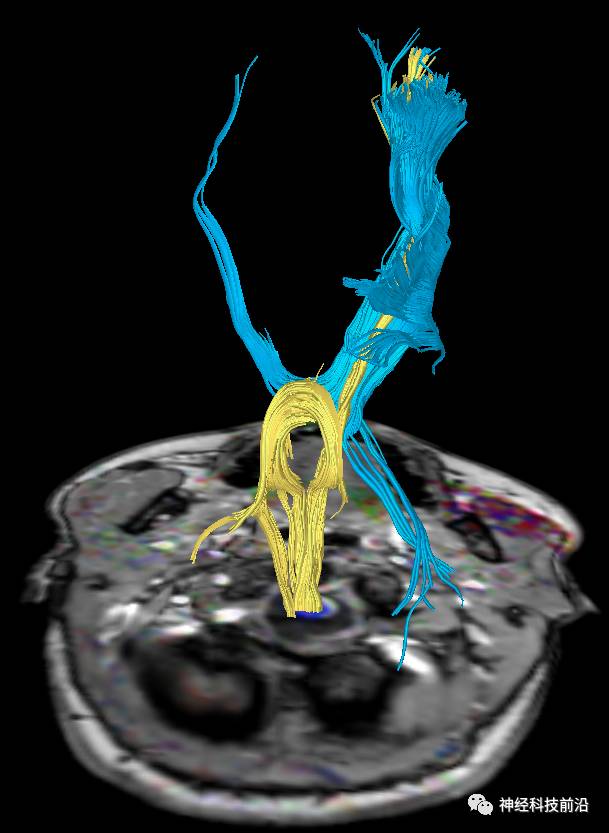

皮质脑桥束与脑干高信号(黄色)纤维束

脑干内高信号为一近环形纤维束,其作用尚待研究。

终上所述:脑干高信号为一近环形纤维束,内囊后肢高信号为皮质脑桥束,皮质脊髓束在中脑位置略靠后。高信号位于中脑前缘,是皮质脑桥束的位置所在,另外有部分桥连纤维。